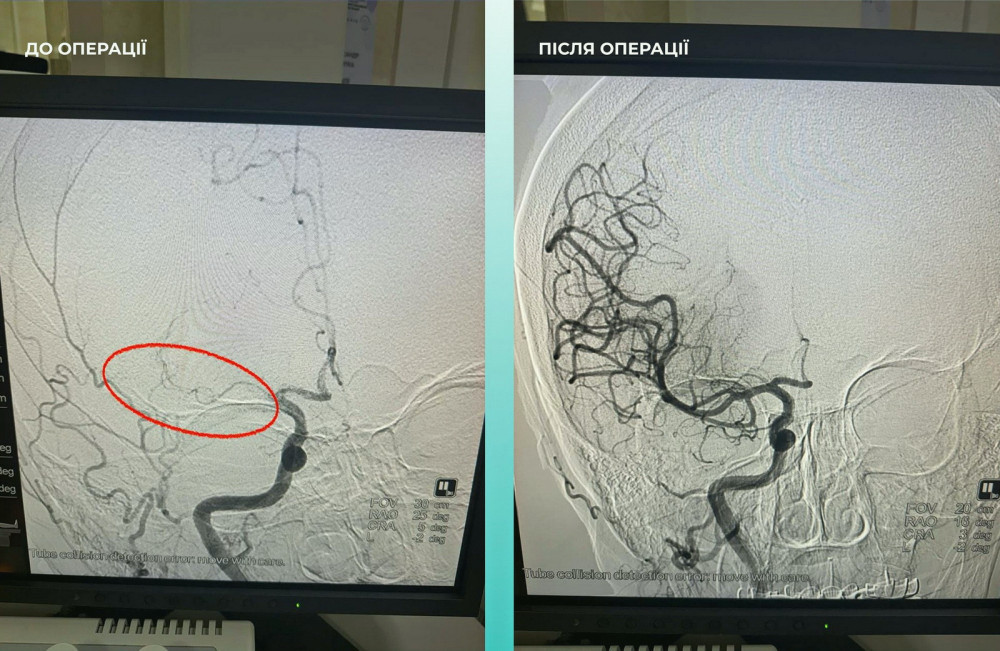

Жінка була доставлена до медичного закладу з тяжким випадком гострого інсульту. Під час комп'ютерної томографії виявили, що середня мозкова артерія була закрита.

Команда лікарів вирішила провести одночасну тромбектомію на обох артеріях, що було вкрай необхідно для порятунку життя.

Операція завершилася успіхом, і пацієнтка почувається значно краще: вона в свідомості і може рухати кінцівками.